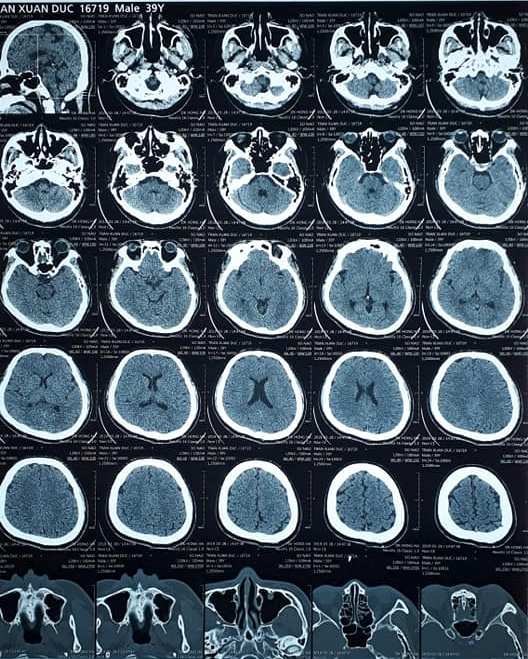

Phim X quang cắt lớp chụp hệ thống xoang trước và sau điều trị:

Bn TXD - nam, sinh năm 1980

Trước điều trị

Sau điều trị

Kết quả hồi phục hoàn toàn sau điều trị